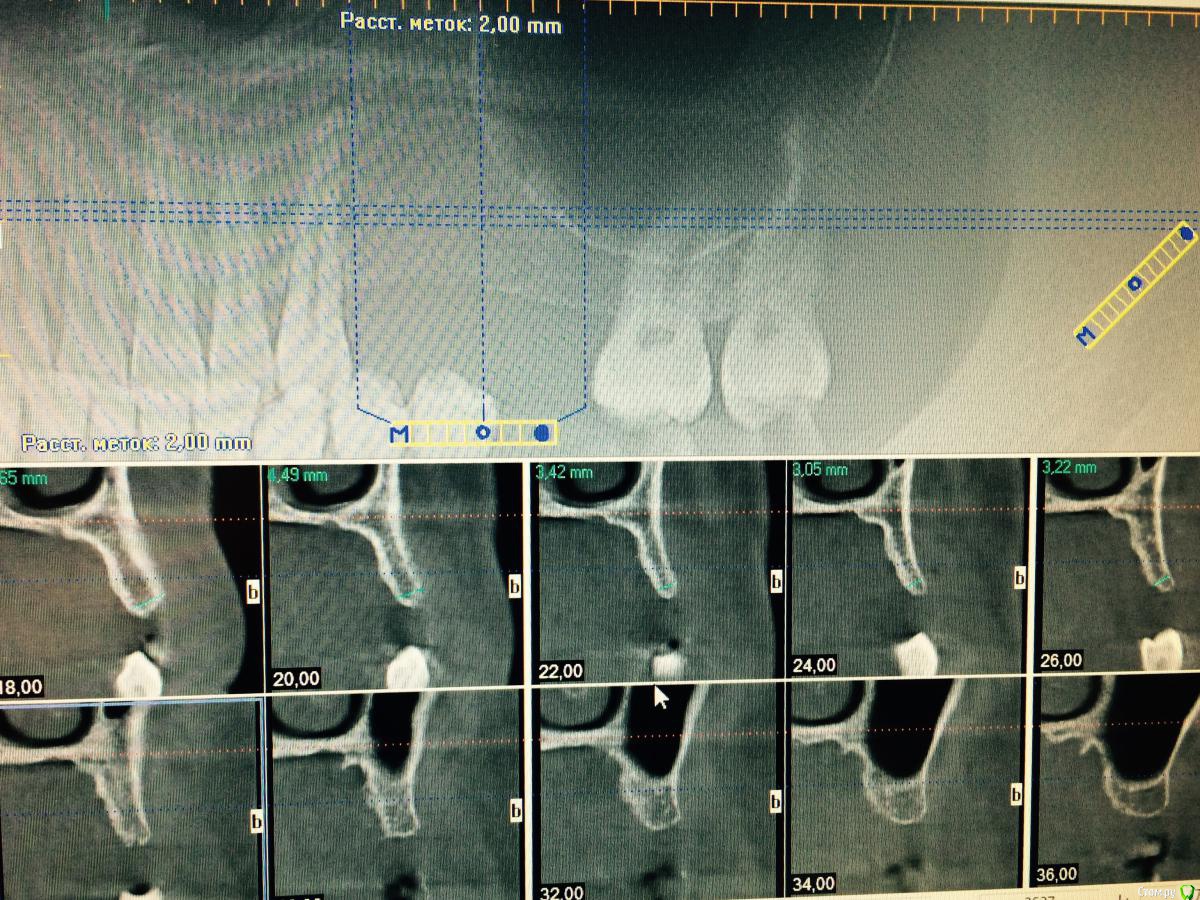

syrovovec Опубликовано 21 сентября, 2015 Поделиться Опубликовано 21 сентября, 2015 Доктора, вот такие стручки на кт. У кого какие мысли? Для правильной ортопедии нужно растить небно? Сосиска(колбаска) пойдет ? Ссылка на комментарий

Sahan Опубликовано 22 сентября, 2015 Поделиться Опубликовано 22 сентября, 2015 Полно кости. Расщепление с имплатацией+сосиска+ССТ. Через полгода контрольное КТ, при необходимости повторно НКР. 1 Ссылка на комментарий

syrovovec Опубликовано 1 октября, 2015 Автор Поделиться Опубликовано 1 октября, 2015 (изменено) К сожалению это все что я могу выжать из Ай кат, если кто подскажет как это сделать буду благодарен Изменено 1 октября, 2015 пользователем syrovovec Ссылка на комментарий